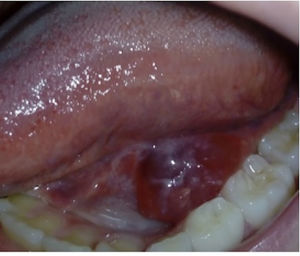

We present the case of a girl aged 9 years referred to our department of pediatric surgery due to recurrent swelling at the base of the tongue with onset five months prior. The examination revealed a fluid-filled tumefaction (Fig. 1). The histopathological assessment confirmed the presence of a unilocular mucous retention cyst with chronic sialadenitis, including acinar atrophy, ductal ectasia and lymphoplasmacytic infiltration. An MRI scan showed bilateral small cysts in the sublingual glands, consistent with simple ranulas, and a multicystic appearance of the parotid glands suggestive of benign lymphoepithelial lesions associated with Sjögren syndrome (SS) (Fig. 2). Laboratory tests revealed elevation of antinuclear antibodies (1:640), high anti-SSA antibody levels (>240 U/mL), and mild elevation of rheumatoid factor (32 IU/mL). Other tests, including serum angiotensin-converting enzyme, protein electrophoresis, immunoglobulin subclasses, complement levels, cryoglobulins, anti-dsDNA, anti-SSB, and anti-U1RNP, were all within normal ranges. The Schirmer test confirmed severely decreased tear production (< 5 mm). The patient later developed sicca syndrome, which improved with symptomatic treatment.